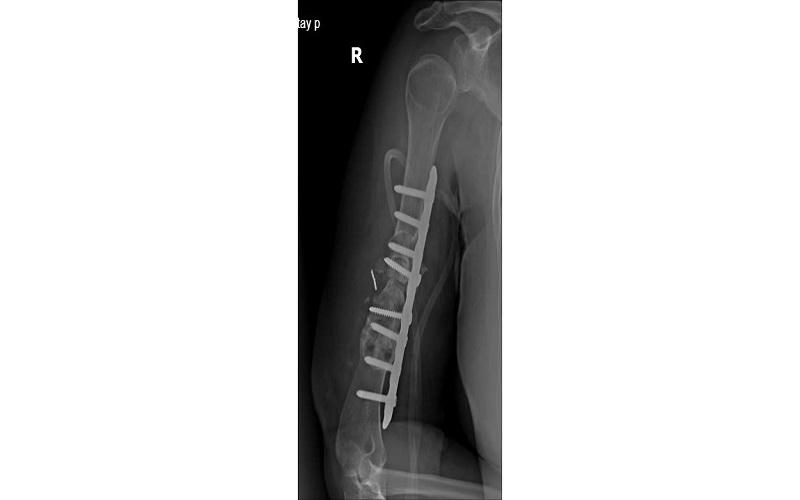

Ngày 18/5/2025, với sự đồng thuận của người bệnh và gia đình, ca phẫu thuật được tiến hành, các bác sĩ tháo bỏ phương tiện kết hợp xương cũ, nạo sạch và làm mới ổ gãy, lấy xương cánh chậu ghép vào ổ gãy, cố định xương bằng nẹp khóa. Sau khoảng 90 phút ca phẫu thuật đã hoàn thành.

![]() |

Tình trạng bệnh nhân sau khi mổ. |